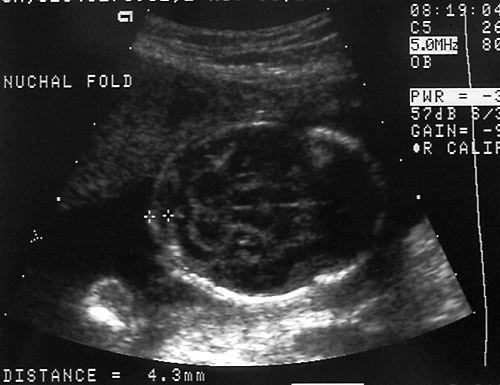

- Nuchal Skin Fold (Benacerraf BR, Frigoletto FD Jr, Laboda LA. Sonographic diagnosis of Down syndrome in the second trimester. Am J Obstet Gynecol. 1985 Sep 1;153(1):49-52)

- Midtrimester (16-22 weeks)

- Edematous integument, with or without fluid collection

- Cut-off value: 6.0 mm